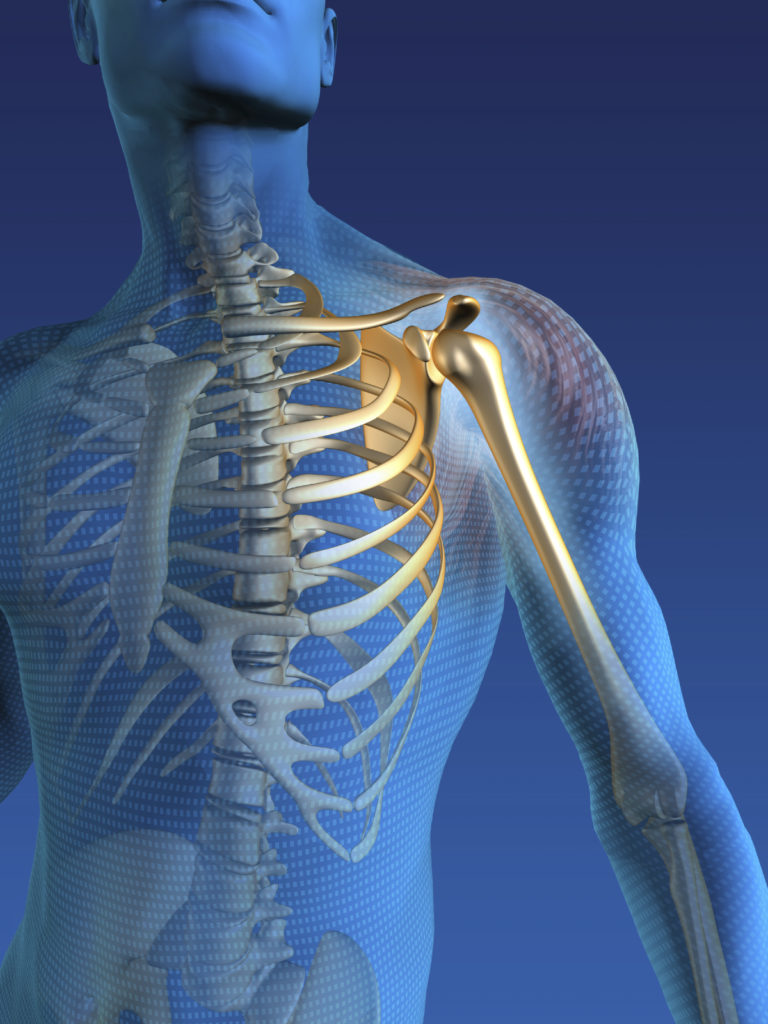

In total shoulder replacement surgery, artificial joint components are inserted to take the place of the bones in the shoulder joint. The shoulder joint is made up of a ball (the rounded end of the arm bone) and socket (the opening at the end shoulder blade). The ball-joint allows for the arm to move in almost any direction.

During total shoulder replacement (sometimes called total shoulder arthroplasty), the rounded limit of the humerus is interchanged with an artificial stem containing a rounded, polished metal head at its extremity. The stem is placed down into the shaft of the arm bone. Cement may be employed to secure the stem in place. Then, a plastic shell-like socket component is implanted with bone cement into the socket (or glenoid) portion of the shoulder blade.